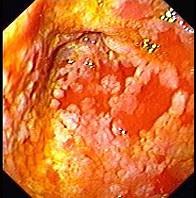

男性,67岁,反复上腹饱胀不适2年,以餐后为甚,伴反酸、嗳气、食欲不振、恶心、呕吐等。胃镜检查胃窦粘膜见散在灰白色斑块,如图:该病人最可能的诊断是 ( )...

问题 男性,67岁,反复上腹饱胀不适2年,以餐后为甚,伴反酸、嗳气、食欲不振、恶心、呕吐等。胃镜检查胃窦粘膜见散在灰白色斑块,如图:该病人最可能的诊断是 ( )

选项 A、胃泌素瘤 B、消化性溃疡 C、慢性浅表性胃炎 D、慢性萎缩性胃炎伴肠上皮化生 E、胃黄斑瘤

答案 D